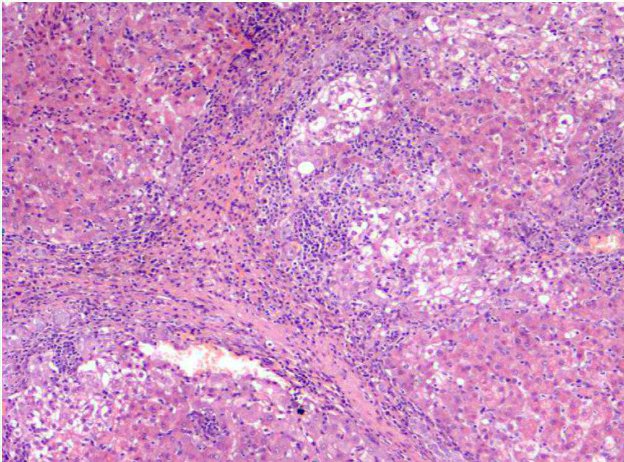

Nella diagnostica di routine l’esame immunoistochimico viene principamente utilizzato per una migliorare caratterizzazione delle neoplasie la cui istogenesi non può essere totalmente definita con la sola valutazione istopatologica.

Per tale scopo vengono utilizzati anticorpi che legano componenti cellulari intracitoplasmatici (es. citocheratine, vimentina), della membrana cellulare (es. CD3, CD20) o nucleari (es. MUM1) che sono specifiche e presenti in una o più popolazioni cellulari. L’utilizzo di uno o, più spesso anticorpi multipli, permette spesso di identificare il fenotipo e l’istogenesi delle cellule neoplastiche.

Figura 2 - Esempio di colorazione immuno-istochemica con CD20 per la confirma e la tipizzazione di un linfoma B-cell.

segnalainoltré che il numero di anticorpi disponibili e di cui è presente una sufficiente letteratura di riferimento in medicina veterinaria, è limitato, e talvolta non è possibile proporre l’utilizzo di marcatori specifici per l’une o l’altra istogenesi.